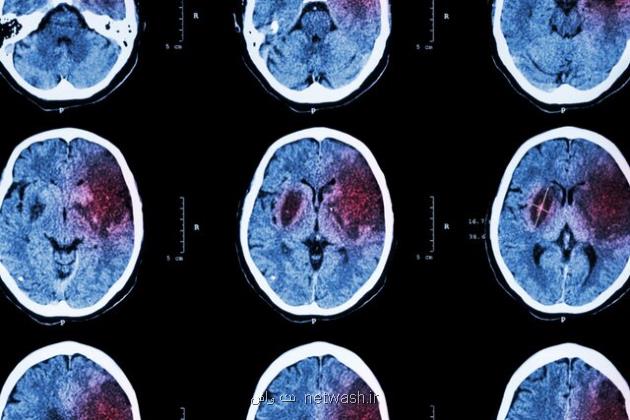

به گزارش نت واش به نقل از ایسنا، به نقل از بنیاد ملی علم ایران (INSF)، سکته مغزی یکی از بزرگترین مشکلات و بیماری هایی است که افراد جامعه را درگیر می کند و عوارض آن در طولانی مدت نمود پیدا می کند. محققان به دنبال راهکارهای برای کاهش عوارض آن هستند و بنیاد ملی علم ایران هم از طرح های در این حوزه حمایت می کند.

«بررسی آثار پیش درمانی بالقوه حاصل از تجویز miRNA-149-5p بر بهبود نقص های نورولوژیک در مدل سکته مغزی رت» عنوان طرحی است که در چارچوب رساله دکتری محمدرضا بیگدلی مسئول آن بوده و سمیرا وحیدی با حمایت بنیاد ملی علم ایران به پایان رسانده است. بیگدلی با مدرک دکتری تخصصی فیزیولوژی از دانشگاه تربیت مدرس در رابطه با این طرح توضیح داد: سکته مغزی بعنوان شایع ترین بیماری عروق مغزی و معضل اولیه سلامت عمومی شناخته می شود که با شیوع و مرگ ومیر بالا، شروع حاد، رشد سریع و نتایج شدید شناخته می شود و متأسفانه میزان بروز آن در حال افزایش می باشد.

وی افزود: سکته مغزی دومین عامل مرگ ومیر و علت اصلی ناتوانی جسمی است. هر سال تقریبا 15 میلیون نفر گرفتار سکته مغزی می شوند و حدود 5 میلیون نفر در سراسر دنیا فوت می کنند. با عنایت به صدمه شناسی زمینه ای، سکته مغزی امکان دارد بعنوان سکته مغزی ایسکمیک یا هموراژیک طبقه بندی شود.

این محقق و پژوهشگر خاطرنشان کرد: 85 درصد کل سکته ها، سکته مغزی ایسکمیک است، درحالی که سکته مغزی هموراژیک علت 15 درصد از سکته ها است. اخیراً، پیشرفت قابل ملاحظه ای در درک مکانیسم های پاتوفیزیولوژی سکته مغزی، بخصوص در سکته مغزی ایسکمیک صورت گرفته است.